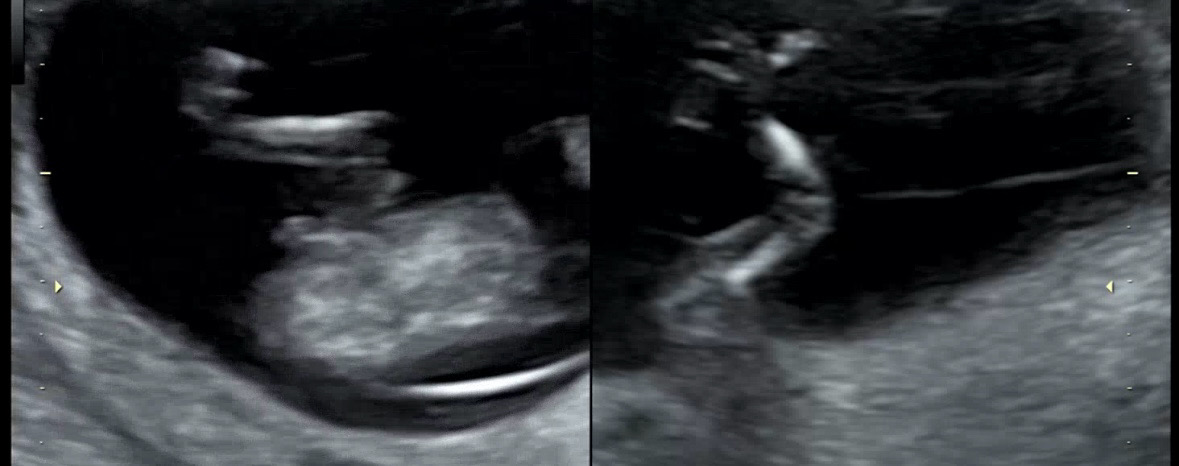

너무 궁금해서…임신 12주차 성별

선생님이 아들같다고 했는데 딸이든 아들이든 너무 감사한데 여러분 생각은 어떠실까요?

이사진에선 안보여용

12주차에성별이 나오나요?

12주 차부터 각도 잘 보이면 알수 있대요 ㅎㅎ 전 각도법 고수는 아니라서 잘 모르겠지만..ㅎㅎ